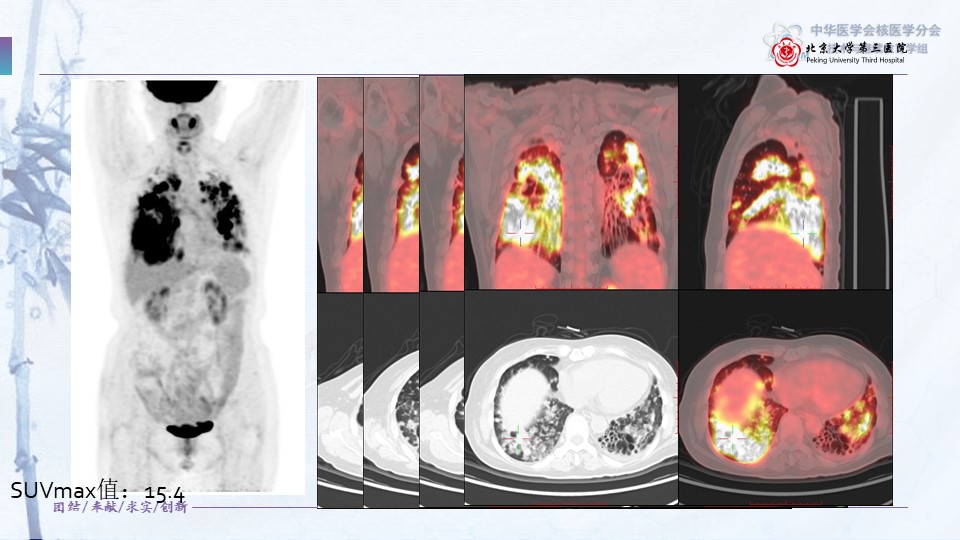

病例87:双肺弥漫性病变PET显像一例-侯小艳